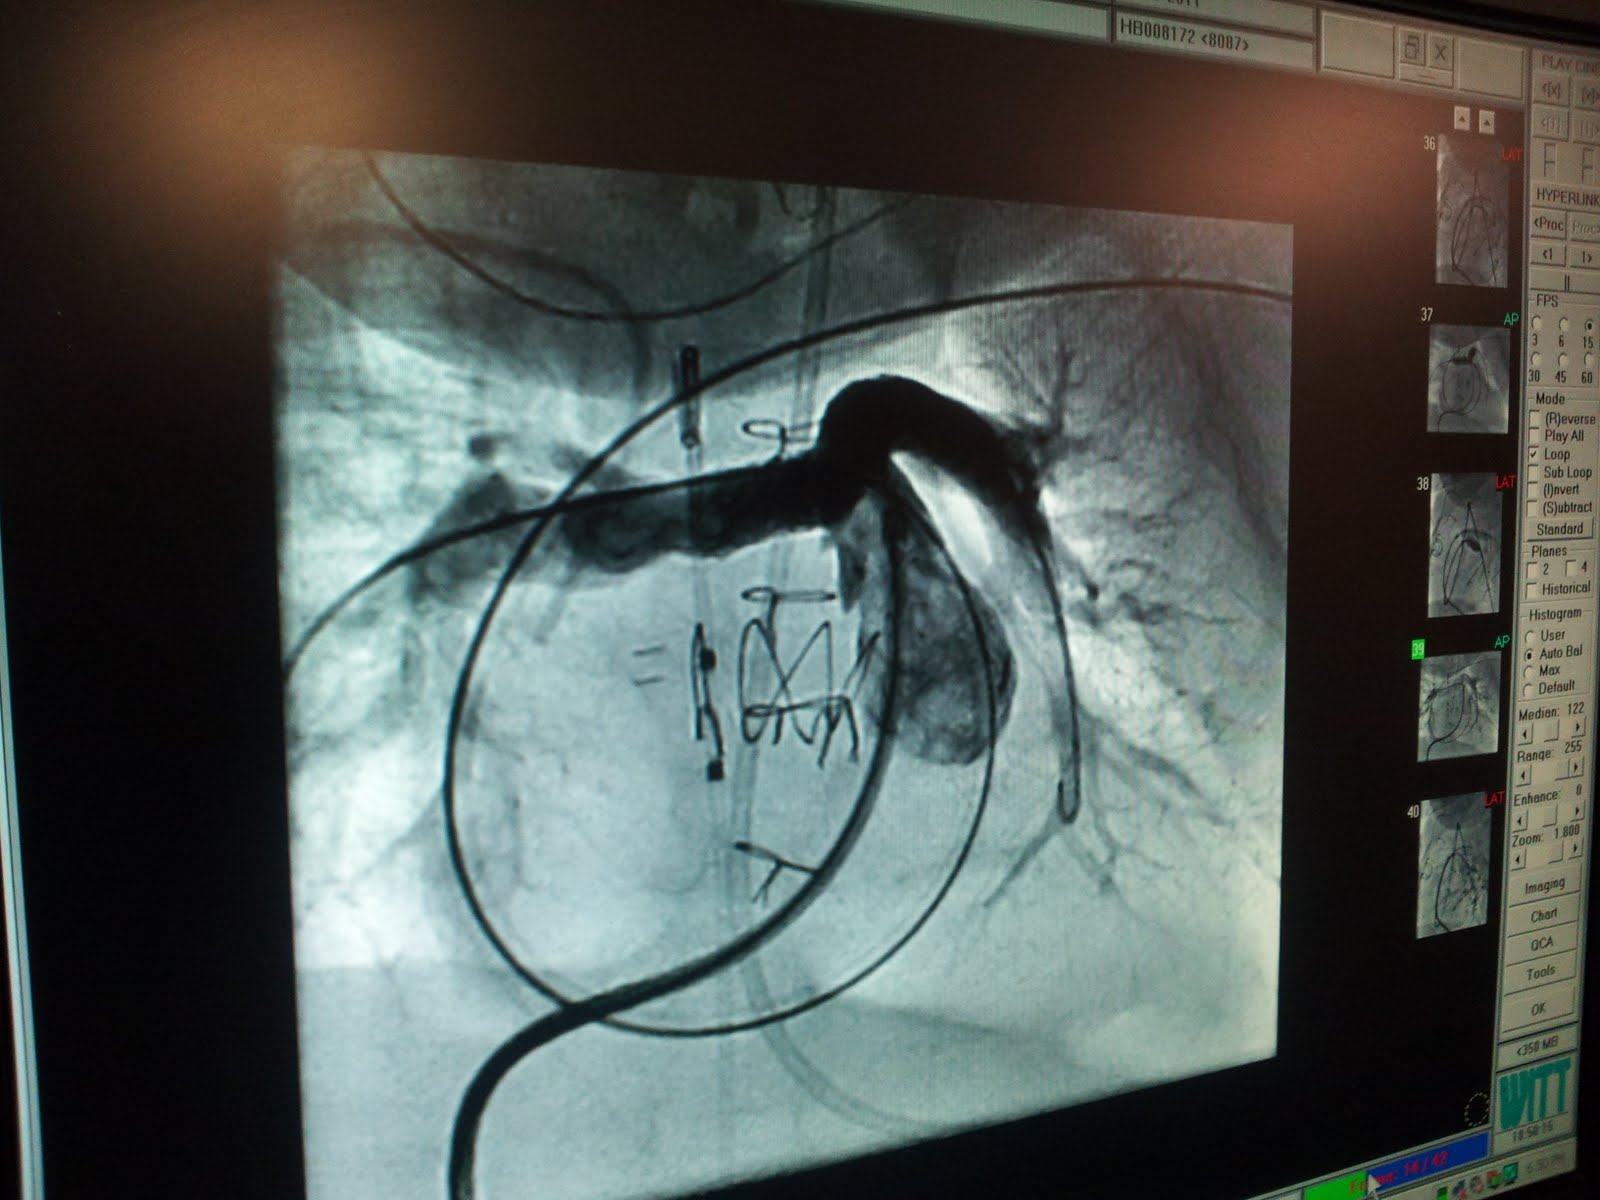

So I will start with Monday's trip to the Cath lab. Like I had shared on Monday there were several objectives for the procedure on Monday. To address the clot near Oakes' liver, and to measure every pressure in and around Oakes' heart. In the Cath lab, once Dr. Murphy gains access into Oakes' arteries and veins he uses one of his sophisticated and itty bitty tools to release dye into Oakes' blood steam and then he can take what I would call an "X-ray video" of the of how Oakes' blood is moving around. When they looked at the blood flow in and around his liver it was normal. No clot present. He had been told by radiology that they clot was causing a 50% blockage, but since there was nothing there he suspected that either the Heparin took care of the clot, or that it was a mis-read by radiology. He thought that it would not have been dislodged because there would have been some kind of residual material left behind and there wasn't. So this is no longer a concern.

Next, Dr. Murphy made his way up to Oakes' heart he began measuring pressures in all of his veins, arteries, and all of the chambers of his heart. He knew that there was congestion where Oakes' left and right pulmonary arteries branched from his main pulmonary artery. and sure enough these pressures were not where they should have been. In fact most of the pressures around his heart were out of sync with each other. So first, Dr. Murphy balloon dilated that LA and RA, once that was completed he remeasured the pressures and learned that the ballooning was not effective. He suspects that either Oakes' tissue where the ballooning took place is very elastic so the ballooning just wouldn't be effective, or there are actual kinks or little folds in the arteries that wouldn't allow them to stay open. Whatever the case, he placed stints in both arteries to keep them open. Once they were placed and Dr. M measured pressures throughout the heart again, all of the pressures were a little elevated but they were now synchronized and even, which is very important. Dr. M showed us the video clips of Oakes' blood flow before stints and after and it was dramatic.